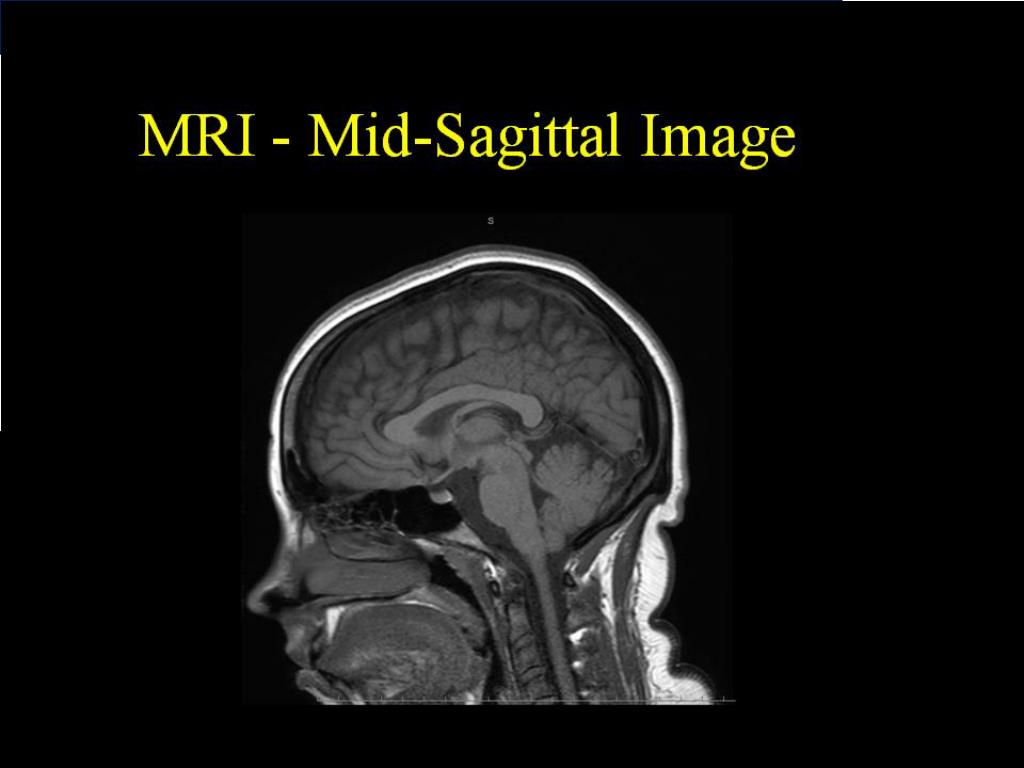

2. The brain (encephalon) is divided into three major divisions. 1) Hindbrain (Rhombencephalon) I. Medulla oblongata II. Pons III. Cerebellum Pons and cerebellum are called as metencephalon. 2) Midbrain (Mesencephalon) 3) Forebrain (Prosencephalon) I. Telencephalon (Cerebrum) II. Diencephalon (between brain)

3. BRAINSTEM oldest part of the CNS. medulla oblongata, pons, and midbrain occupies the posterior cranial fossa of the skull. stalklike in shape and connects the narrow spinal cord with the expanded forebrain.

4. BRAINSTEM contains 10 cranial nerves, and most of the motor and sensory systems pass through this important region. a relatively small region (approximately 7 cm long) links the forebrain (i.e., cerebral cortex) and spinal cord and all messages going between the two areas must go through the brain stem.

5. Midbrain 2 cm in length connects the pons and cerebellum with the forebrain. cerebral hemispheres connected to brainstem by 2 large fiber tracts cerebral peduncles The dorsal aspect of the midbrain the tectum(L., roof] paired superior and inferior colluculi(singular, colliculus). corpora quadrigemina superior colliculicenters for visual reflexes inferior colliculilower auditory centers Tegmentum: Anteriorpart of midbrain BetweenCerebralaqueduct

6. Midbrain The midbrain comprises two lateral halves cerebral peduncles anterior part: crus cerebri substantianigra posterior part: tegmentum